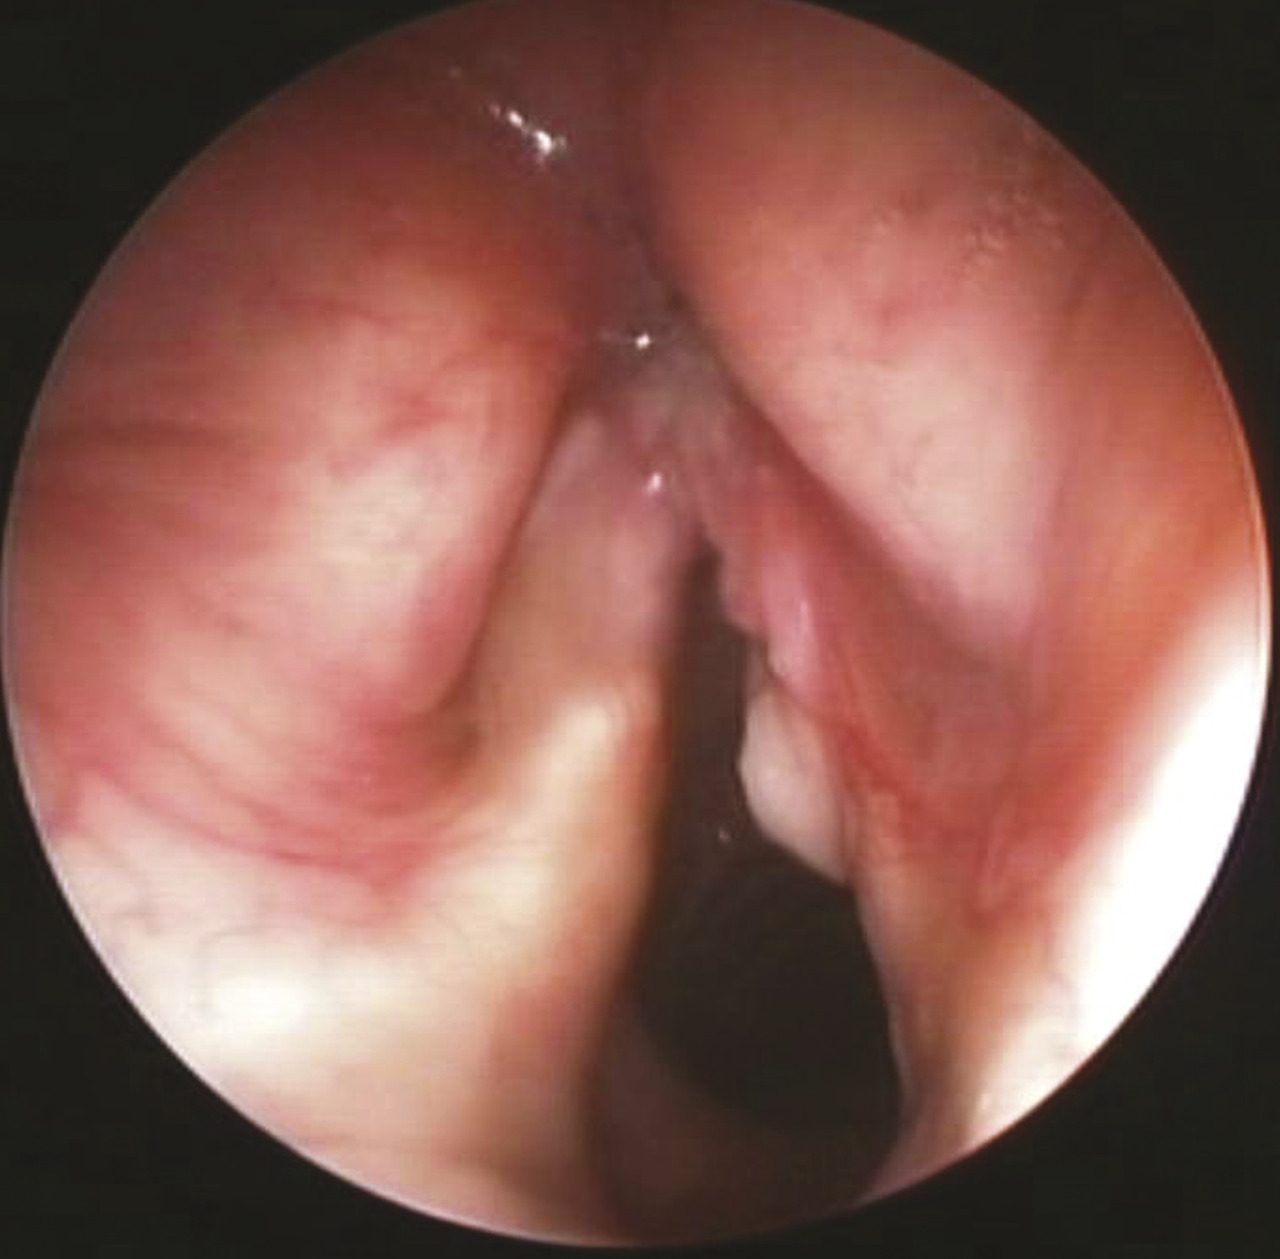

Au stade précoce, il existe rapidement une dysphonie, qui doit faire l’objet d’une exploration par endo­scopie au-delà de trois semaines d’évolution s’il existe des facteurs de risque (fig. 10). Celle-ci peut évoluer vers une dyspnée ou une dysphagie. Les autres signes ne sont pas spécifiques : gêne, sensation de corps étranger, dysphagie, voire otalgie ou douleur à la déglutition dans les stades plus évolués. L’apparition d’une dysphonie prolongée chez un patient tabagique impose un examen spécialisé ORL par nasofibroscopie.

Le larynx est une région anatomique de petite taille hautement fonctionnelle – respiration, phonation, déglutition –, ce qui rend son exploration par imagerie délicate. La TDM présente le meilleur compromis d’exploration du fait de la finesse des coupes et de la rapidité de la technique, diminuant les artefacts liés aux mouvements. Une acquisition de qualité en respiration douce est particulièrement importante pour l’exploration de la surface des cordes vocales en position neutre ; une acquisition ciblée en phonation, en faisant prononcer au patient le son continu [e], permet la recherche d’une extension supraglottique d’une tumeur glottique.